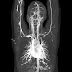

10. CT Angiography: brain, heart, lung, kidney, extremities